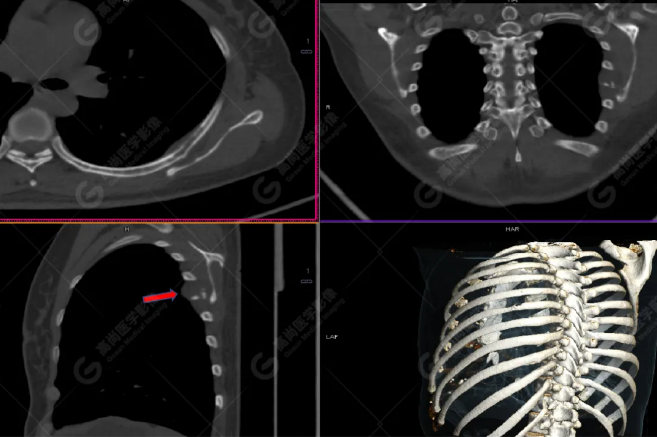

PET/CT影像圖

胸椎溶骨性骨質(zhì)破壞,F(xiàn)DG環(huán)狀代謝增高,SUVmax為4.0。